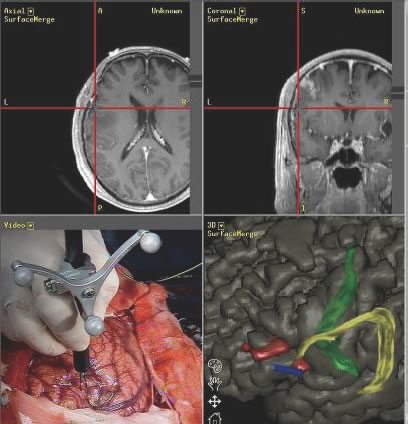

像汽車導(dǎo)航(汽車導(dǎo)航,或者GPS)一樣,在腦腫瘤的手術(shù)中導(dǎo)航系統(tǒng)也是有用的。因為能夠?qū)崟r知道手術(shù)的部位在圖像上的位置,所以手術(shù)者可以判斷到重要的腦區(qū)和神經(jīng)纖維的距離有多遠,能順利地切除到哪里(圖1)。

另外,在將重要的腦區(qū)域神經(jīng)纖維和血管的分布等與腫瘤的圖像和手術(shù)中的圖像相融合的腦映射技術(shù),也在支持著順利可靠的手術(shù)(圖2-3)。

圖1:神經(jīng)導(dǎo)航系統(tǒng)。通過在手術(shù)中展示腫瘤、重要的腦區(qū)、神經(jīng)纖維的位置信息,使手術(shù)更加順利可靠。

圖3:融合三維圖像的腦功能映射